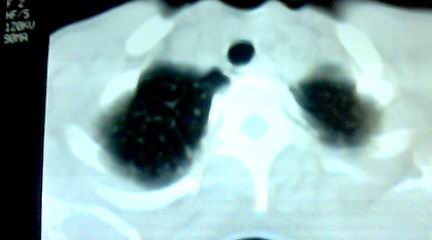

标题: CT25218:请教!胸部CT,胸8椎体骨质破坏,伴周围软组织肿。

患者,女41岁,肢体乏力。

双肺及胸椎结核。

双肺及胸椎结核。支持!